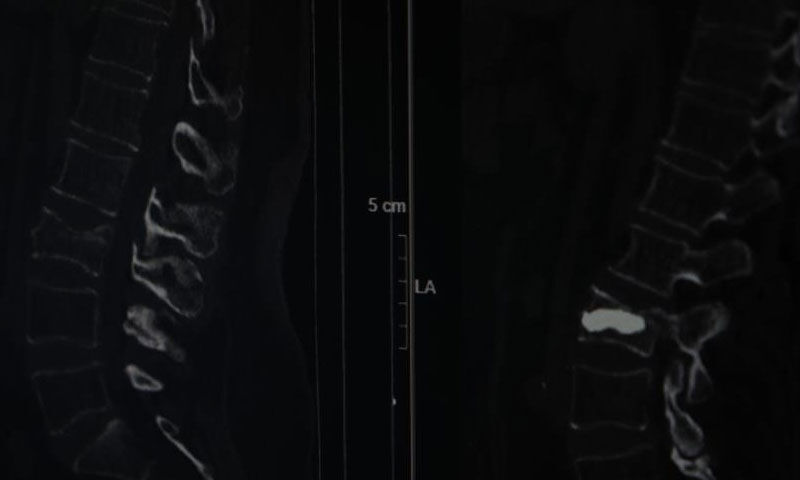

İstanbul'un Sarıyer ilçesinde Kilyos'taki evinde tek başına yaşayan 2 çocuk annesi emekli mali müşavir olan 76 yaşındaki Alis Armağan, iddiaya göre ağustos ayında evinin bahçe kapısının önünde düştü. Düşme sonrası omurganın bel bölgesinde kırık meydana geldi ancak Armağan ağrılarını bel fıtığına bağladı. Bir süre bu şekilde düşünen Armağan, ağrıları geçmeyince hastaneye başvurdu. Burada Beyin ve Sinir Cerrahisi Uzmanı Doç. Dr. Şevket Evran ve ekibinin yaptığı incelemelerde kemik erimesine bağlı kırık tespit edildi.

Armağan, durumu şaşkınlıkla karşılarken doktorlar operasyon gerekliliğini ifade etti. Genellikle kemik erimesine bağlı omurga kırıklarını tedavi etmek amacıyla uygulanan minimal invaziv bir cerrahi yöntem olan ve hastanın aynı gün normal yaşamına dönebilme imkanı sunan kifoplasti operasyonu 25 Ağustos günü gerçekleştirildi.

Yaşadıklarını anlatan 76 yaşındaki Alis Armağan, "Bahçe kapısının önünde düştüm, ne olduğumu anlayamadım. Hiçbir yerimde ne çizik ne morartı var, öyle bir düşme. Herhalde 2 tane fıtığım var, düşmeyle onlar yine nüksetti dedim. İğneler oldum, geçmeyince bu başka bir şey diyerek doktora müracaat ettik. Hemen de ayaklandım, Allah'a şükür, her gün doktoruma dua ediyorum.Allah kimseye böyle sıkıntılar vermesin, hele ileri yaş için çok zor. Düşmem ağustos başıydı, ameliyat 25 Ağustos'ta oldu, fıtık filan diyerek oyalandım. Sonra MR çekildik, tespit edildi. Yoksa ameliyat öncesi perişandım. Bu yaştan sonra ameliyat mı olur dedim, herkes de yaşlılar çok zor, çok riskli diyor. Hastaneye çok umutsuz geldim ama iyi çıktım" diye konuştu.

"Omurga kırıklarını menopoz sonrası kadınlarda sıklıkla görüyoruz" diyerek sözlerine başlayan Doç. Dr. Evran, "Bu hastalarda travma sonrası kemik yoğunlukları düşük olduğu için omurgalarında kırık oluşma ihtimali normal popülasyona göre çok daha fazla görülüyor. Travma geçiren menopoz sonrası bir insanda kemik yoğunluğuna daha önce dikkat etmemiş, bununla ilgili daha önce tedavi almamışsa bu hastalarda travma sonrası oluşan, bel, sırt, boyun ağrılarında özellikle bu kırıklar düşünülmekte. Bir beyin ve sinir cerrahisi hekimine başvurmaları önerilmekte. Vücudun daha çok yük taşıyan bel ve sırt bölgelerinde oluşuyor. Hasta sırt veya bel ağrısıyla travma sonrası başvurduğu zaman önce gerekli tetkiklerini yapıyoruz. Görüntülemelerinde kırığı tespit etmiş olursak ve bu bir travma sonrası gelişen bir kırıksa bu kırıkta öncelikle omurgadaki çökme miktarının derecelerine bakıyoruz. Derecelere göre korse, yatak istirahati gibi tedavileri öncelikle deniyoruz. Fakat kırığın çökme derecesi çok ileriyse veya omuriliğe bir zarar söz konuysa daha minimal invaziv olarak tedaviler ve daha ileri hastalarda cerrahilerle omurgaya enstrümantasyonlarla tedavi edebiliyoruz" dedi.